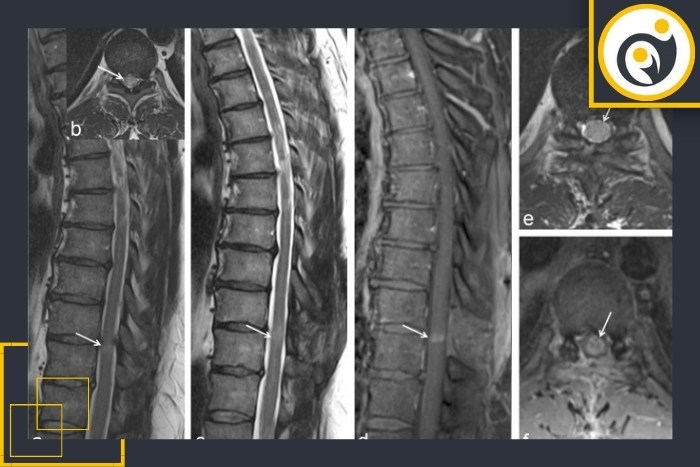

درد شدید و کنترلنشده بهویژه اگر همراه با ضعف پا باشد میتواند نشانه خونریزی، التهاب شدید یا عارضه جراحی باشد و انجام MRI زودهنگام را ضروری میکند.

اگر پس از یک دوره بهبود درد سیاتیکی دوباره ظاهر شود یا شدت بگیرد احتمال عود دیسک مطرح میشود و تصویربرداری تکمیلی باید انجام شود.

بروز بیحسی پیشرونده، گزگز شدید، ضعف عضلانی جدید یا اختلال در راه رفتن از علائمی هستند که نیاز به بررسی تصویربرداری دارند.

این علائم از موارد اورژانسی محسوب میشوند و باید فوراً با MRI بررسی شوند زیرا میتوانند نشانه آسیب جدی به اعصاب نخاعی باشند.

اگر پس از این بازه زمانی درد یا محدودیت عملکردی باقی بماند تصویربرداری ارزش تشخیصی بیشتری پیدا میکند و به تصمیمگیری درمانی کمک میکند.

تب، درد مداوم، قرمزی محل جراحی یا افزایش درد شبانه میتواند مطرحکننده عفونت باشد و بررسی تصویربرداری را ضروری کند.

قبل از اقدامات درمانی پیشرفته یا جراحی مجدد تصویربرداری تکمیلی انجام میشود تا علت دقیق علائم مشخص شود.